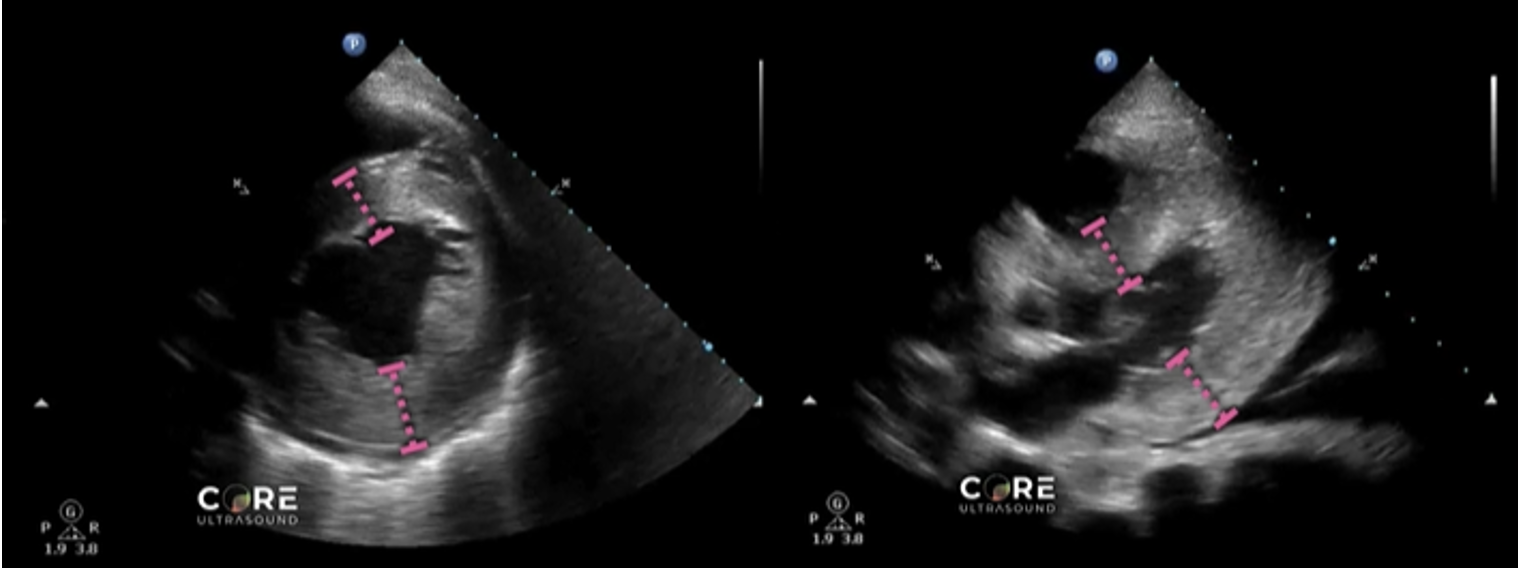

Finding #2: Asymmetrical septal hypertrophy

• View: PSL or PSS View

• Look for a ratio between the interventricular septum/posterior wall thickness

• Ratio > 1.3 in normotensive patients is consistent with HCM

• Ratio > 1.5 in hypertensive patients is consistent with HCM

Left image shows how to measure the septal wall and LV wall in the PSS view. Right image shows the same in the PSL view.